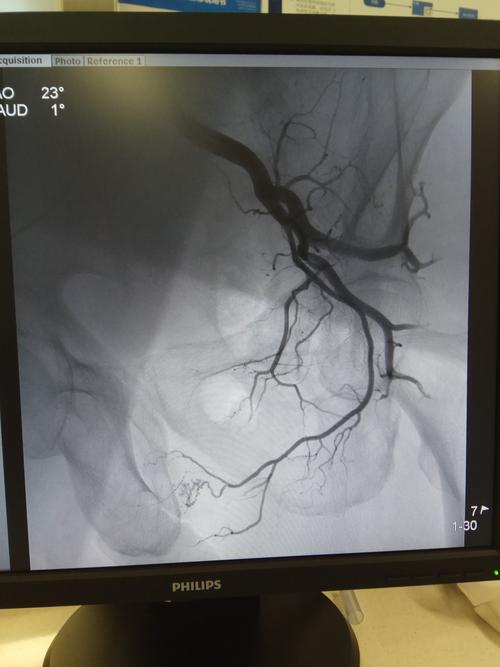

前列腺动脉血管造影图

前列腺动脉血管造影图,前列腺动脉血管解剖

造影发现前列腺动脉,走行扭曲,增多.

介入微创治疗前列腺增生新方法—超选择插管前列腺动脉造影术 动脉

术前血管造影可见右侧前列腺血管丰富,前列腺染色明显